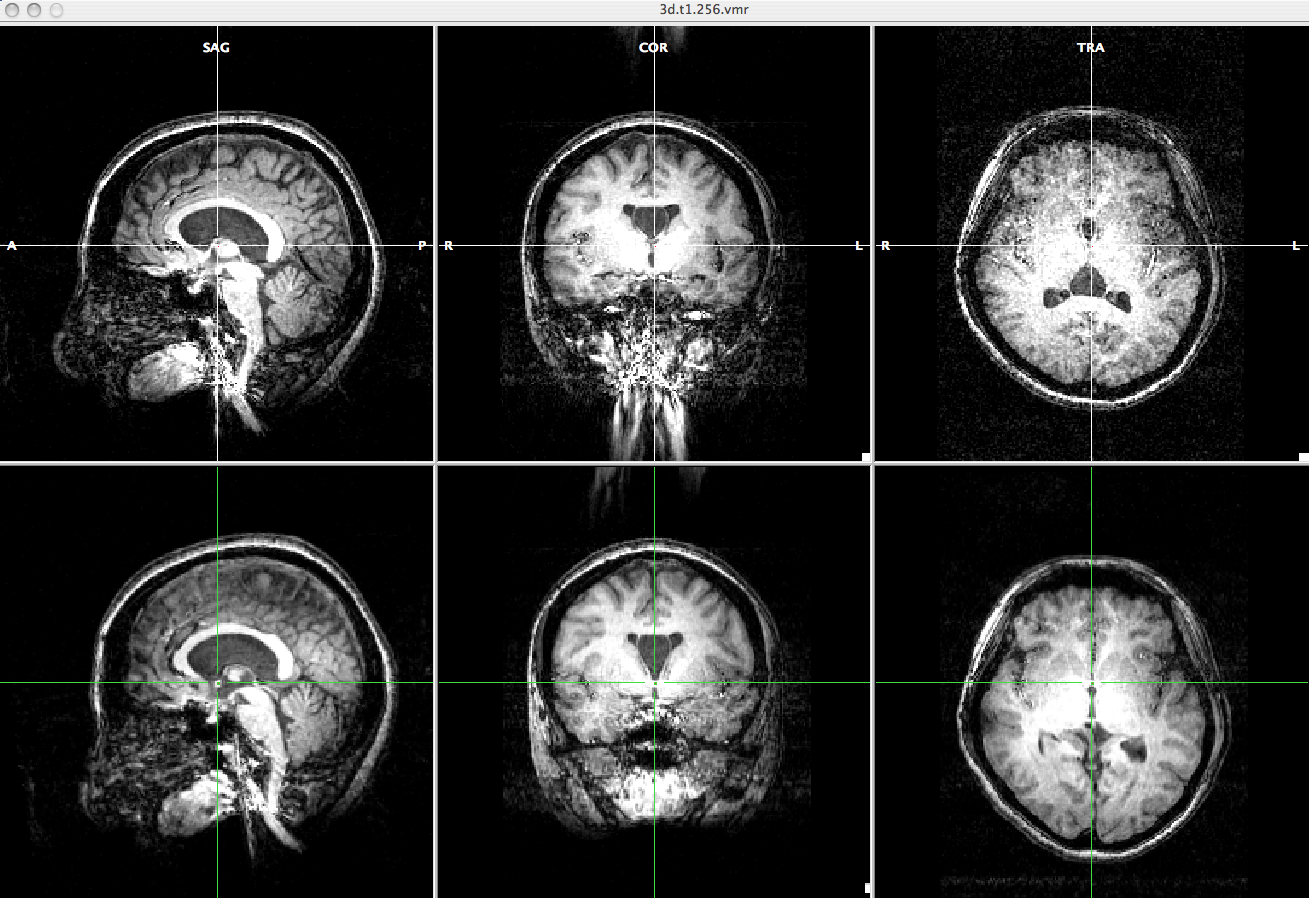

Fig2.png